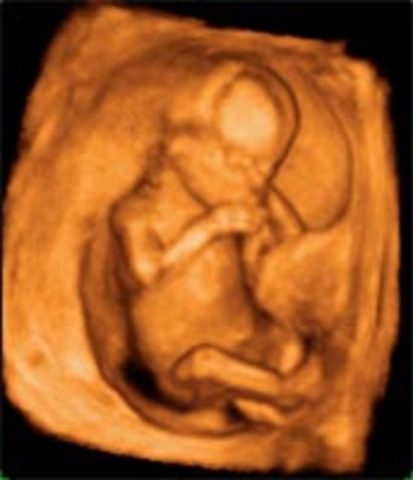

A partir de esta semana comienza el periodo fetal, el cual se caracteriza por un rapido crecimiento y finaliza el periodo de formación de orgános.

Termina el primer trimestre del embarazo, mide entre 6,5 a 8 cm